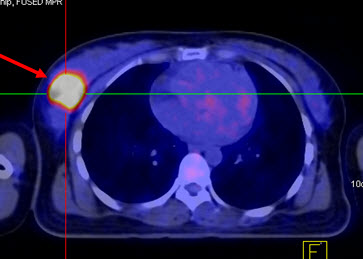

2. Chẩn đoán phân loại giai đoạn hạch nách, xác định giai đoạn bệnh:

Ung thư vú nguyên phát có thể được chia làm hai giai đoạn. Giai đoạn khu trú tại vùng (vú và hạch nách) và giai đoạn di căn xa. Di căn hạch nách là một trong những yếu tố tiên lượng quan trọng nhất giúp các bác sĩ lựa chọn phác đồ điều trị bổ trợ đúng. Nếu không có di căn hạch nách thì không cần thiết phải lấy bỏ hoàn toàn hạch nách, tránh nguy cơ phát triển chứng phù hạch (12%), chứng rối loạn chức năng và sự không thoải mái xảy ra ở hơn 50% những bệnh nhân sau khi vét hạch nách.

Hình 2a: Hình PET toàn thân của bệnh nhân Đỗ Thị N., 87 tuổi. thấy khối u ở vú phải (mũi tên đỏ) và hai hạch nách phải (mũi tên xanh) tăng hấp thu FDG.

Hình 2b: cho thấy rõ mức độ tập trung cao FDG tại vùng có khối u ở vú phải, max SUV=10,24.

Hình 2c: cho thấy hình ảnh hai hạch nách tăng hấp thu FDG (hạch di căn ung thư vú).